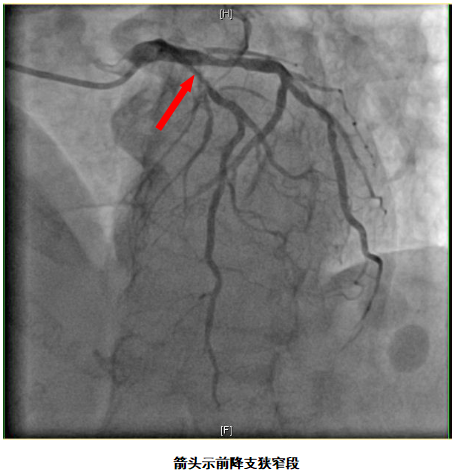

79岁的娄大妈近两个月来间断出现胸痛的症状,心内科就诊考虑“冠心病”,做冠脉造影,发现她的前降支血管有超过75%的狭窄,同时狭窄处有弥漫性钙化,心内科充分评估后,建议行外科搭桥手术。